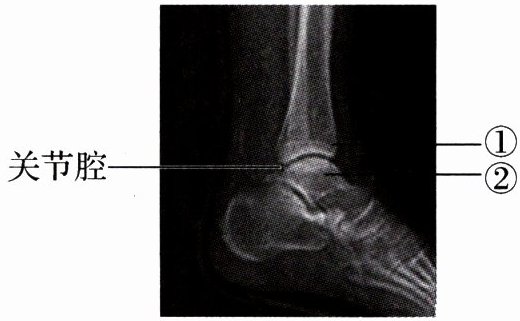

4. (河北中考)右下图为某人左脚的踝关节射线透视图像,①②表示踝关节内的结构。下列说法错误的是(

A.①是关节头,②是关节窝

B.①②表面覆盖着关节软骨

C.关节腔内有滑液,使关节灵活

D.踝关节在运动中起枢纽(支点)作用

A

)。A.①是关节头,②是关节窝

答案:

A 解析:关节面包括关节头和关节窝,由题图可知,①是关节窝,②是关节头。